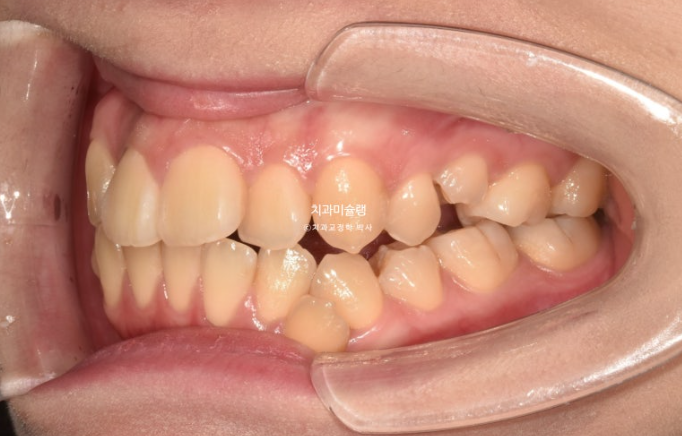

23년 10월 교정치료를 이해 온 30대 환자분입니다.

약 2mm 정도의 중심선 불일치 그리고 덧니가 보입니다.

개방교합도 있고

30년간 공간이 없어서 미처 내려오지 못한 작은어금니도 있습니다.

덧니가 워낙 심해 작은어금니 4개 발치가 불가피한 상황입니다.